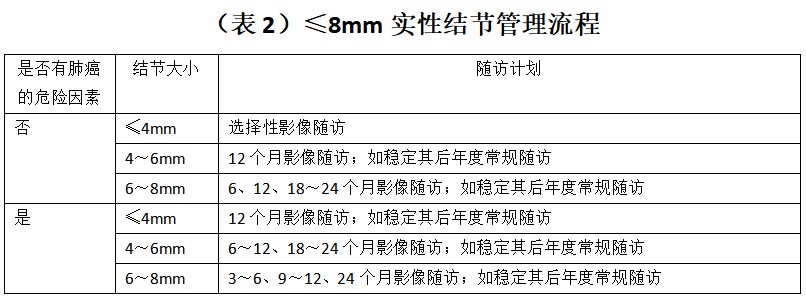

总结临床上,尽管肺结节的评估手段是多元化的,包括病史、影像学检查、肿瘤标志物检查、功能显像以及一些有创检查和手术,但临床上医生最可及的是病史、胸部 CT,部分医院可完成肿瘤标志物检查,费用在几百元不等,有一定参考价值。但对于 PET-CT,因其费用较高,作为常规评估比较困难。有创的评估检查手段主要是针对前面几种方式综合评估为高危的患者所采取的方法,临床普及性不强。因此,肺部结节究竟是手术还是随访,如何进行随访重点在于病史和胸部 CT,综合评估肺结节恶性概率、结节大小、密度、是单发还是多发等多种因素,制定个体化治疗及随访方案。